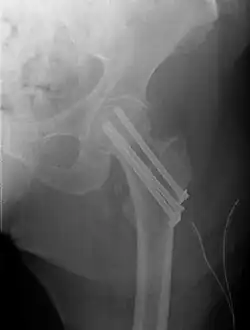

| Intertrochanteric hip fracture in a 17-year-old male | |